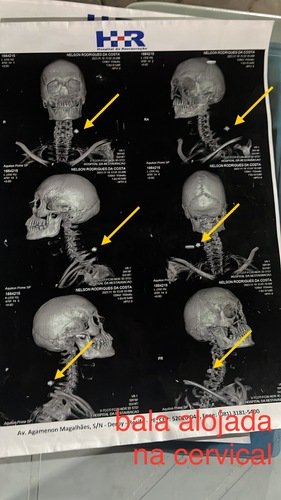

A alguns meses atrás fui demitido da empresa porém 20 dias apos a demissão acabei levando 3 tiros em um atentado, um na perna um no braço e outro na cabeça ficando 2 alojada, uma no ombro e outra na cervical, ocasionando atrofia da perna e perda do movimento do pé esquerdo e atrofia e perda do movimento da mão direita.